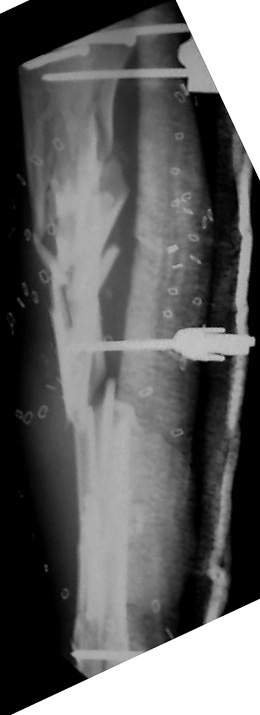

Tibia Fx ForumCase 1

I would appreciate treatment suggestions.My patient is a 30 year old with a very comminuted tibia fracture 6 weeks ago.It was grade 3B open. Initial treatment included irrigation, debridementClick images to enlarge.

and a hybrid external fixator including femur, tibia and foot. Screwswere placed in the plateau and plafond and a free flap plus STSG. Theskin is ok but atrophic. The femoral pins were removed and knee motionstarted at 6 weeks. There is no sign of callus. There is one pin inthe one large fragment of the diaphysis. All the pieces are lined upreasonably well. The XF pins are ok. Suggestions? Thank you.